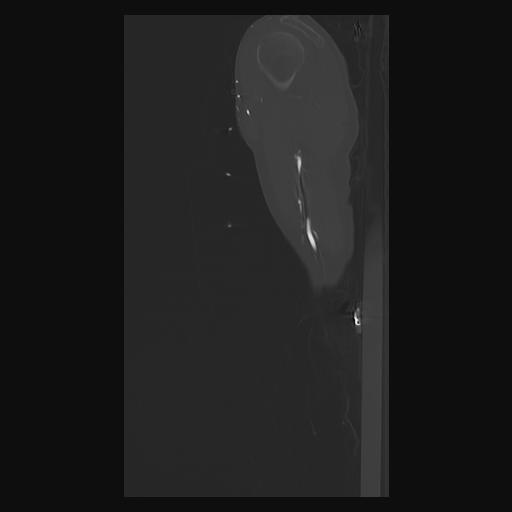

33 PULMON,CE,Sagittal,3.000,PULMON,Sagittal,